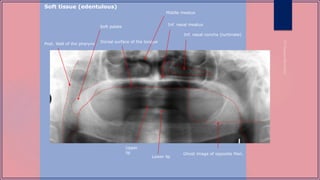

Panoramic radiograph of an edentulous

patient. The true image of the right

mandibular angle is outlined by white

arrows. The ghost image of the same

structure is outlined using black arrows.

Detail of panoramic radiograph showing how the

shadow of the spine can obscure detail of the

mandibular anterior teeth if the patientís neck is not

kept erect during panoramic radiography

Inf. nasal concha (turbinate)

Inf. nasal meatus

Dorsal surface of the tongue

Post. Wall of the pharynx

Soft palate

Lower lip

Upper

lip

Middle meatus

Ghost image of opposite Man.

Soft tissue (edentulous)